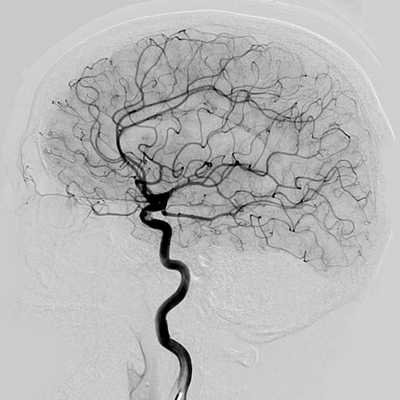

Отличия МРТ и КТ ангиографии от классической ангиографии

МРТ и КТ ангиографию не следует путать с прямой ангиографией. Классическая ангиография - это технологически простой метод исследования. Он появился в 1927 году, когда португальский невролог доктор Мониц провел первое ангиографическое исследование с введением контрастного вещества. Долгое время этот метод оставался золотым стандартом обследования сосудов головы, сердца, позвоночника, шеи, нижних конечностей и брюшной аорты. Основным недостатком данного вида ангиографии является необходимость сделать механический прокол сосудов (сонной или бедренной артерии), чтобы ввести контрастное вещество и обследующее устройство. Прямая АГ- это, в конечном счете, инвазивная манипуляция, требующая госпитализации и имеющая определенный риск осложнений. Кроме того, классическая ангиография дает возможность делать ангиограммы только в прямой или боковой проекции.

У прямой агиографии есть и диагностические ограничения. С ее помощью врач может достаточно подробно рассмотреть сами сосудистые аномалии (стеноз, окклюзии), но по ней нельзя получить информацию о мальформациях артерий, тромбозах вен, характере кровоизлияния при инсульте, состоянии вещества головного мозга. Для этого потребуется КТ или МРТ сосудов головного мозга.

- Ангиографию. Церебральная ангиография позволяет установить расположение, форму и размеры аневризмы. В отличие от рентгенологической ангиографии магнитно-резонансная (МРА) не требует введения контрастных веществ и может проводиться даже в остром периоде разрыва аневризмы сосудов головного мозга. Она дает двухмерное изображение поперечного сечения сосудов или их объемное трехмерное изображение.